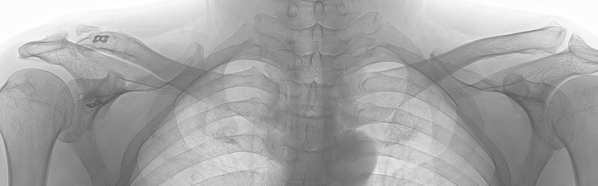

その後術後2年で来院をされ、ふたたびレントゲンを撮影しました。

術後2年のレントゲンが下の写真です。

右鎖骨の形は左と違うのは受傷から20年以上たっているために変形がすすんでおりました。手術の際には変形している関節には操作はしないで、靱帯移植と金属ボタンを設置する方法だけをほどこしました。経過良好ですと力強くおっしゃってました。